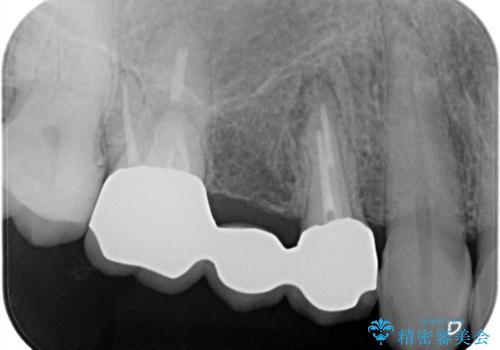

歯肉を押すと痛みがあり、レントゲンの画像でも病変があることがわかります。

前医にてラバーダムを用いた根管治療が完了していたため、歯根の先端を切除する治療を行いました。

6ヶ月経過し、症状もなくなり、病変も縮小していることが確認できます。